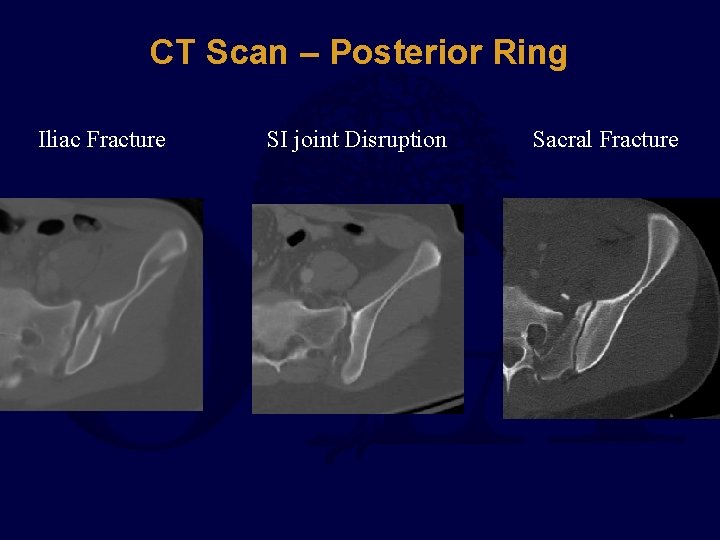

CT Scan – Posterior Ring Iliac Fracture SI joint Disruption Sacral Fracture